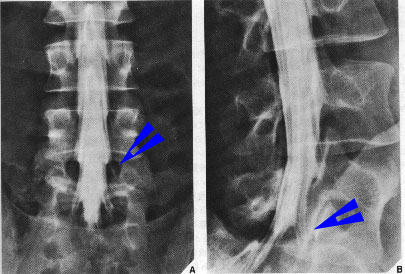

レントゲン写真では骨しか写りませんが造影剤を脊髄神経の包まれている袋に注射することで神経の状態が白い帯状になって現れています。

脊髄は神経根という枝を出しますが、脊髄腔造影像では青い矢印のように写ってきます。